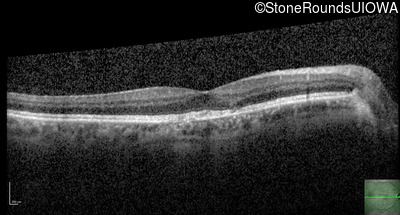

Optical Coherence Tomography - Left - 20/40 +1

Exemplar / OCT Stack